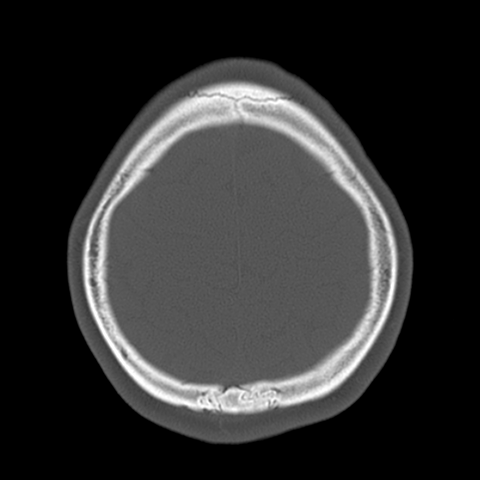

Upper calvarial vault [3 of 7]